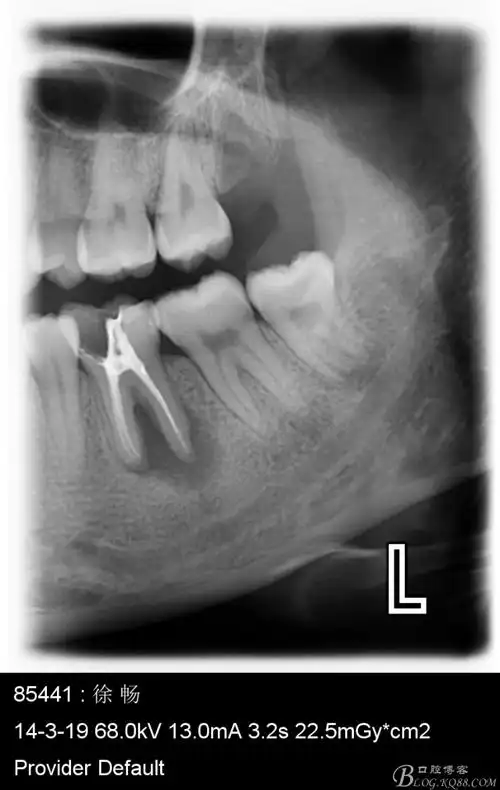

最近几例根尖阴影比较大的根尖周炎

从而导致脓肿,也就是牙根顶端的局部感染,诱发牙髓炎和根尖周炎

牙齿急性根尖周炎感染可能引起间隙感染,是相当危险的一件事情.